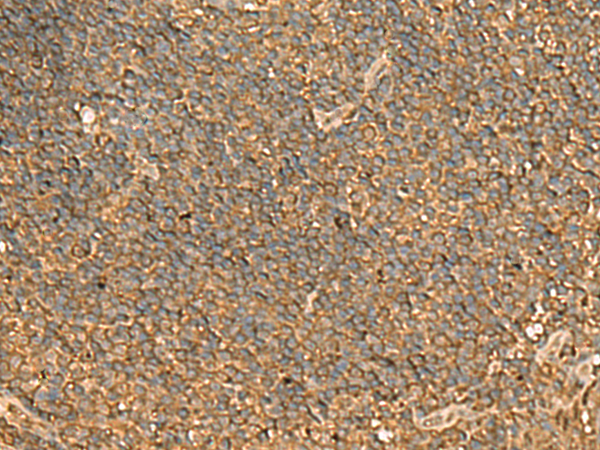

分类: 科研抗体货号: P02882别名: LMP10; MECL1; beta2i应用: WB,IHC反应种属: Human, Mouse, Rat